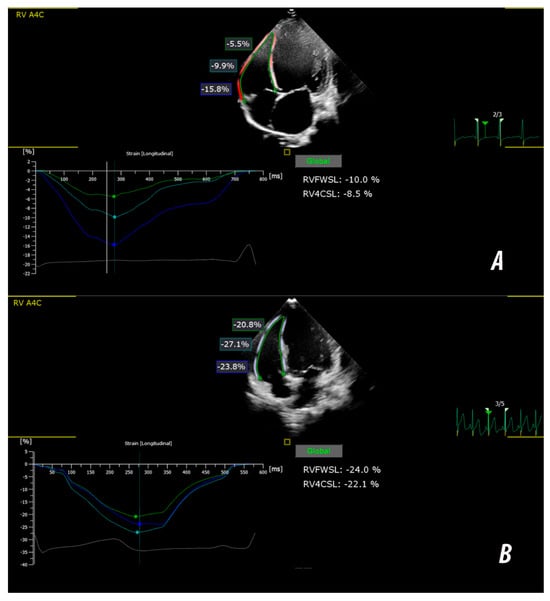

Basal-Predominant Right-Ventricular Dysfunction in Pediatric Dilated Cardiomyopathy: An Integrated Biventricular Strain Analysis

Iolanda Muntean, Diana Ramona Iurian, Asmaa-Carla Hagau and Beatrix-Julia Hack

Biomedicines 2026, 14(1), 38; https://doi.org/10.3390/biomedicines14010038 - 23 Dec 2025

Background: Right-ventricular (RV) involvement is starting to gain recognition in pediatric dilated cardiomyopathy (DCM), but its deformation characteristics and its relationship to functional status remain insufficiently defined. Methods: Twenty-nine children with primary DCM were compared with age- and sex-matched healthy controls. Conventional echocardiography

Background: Right-ventricular (RV) involvement is starting to gain recognition in pediatric dilated cardiomyopathy (DCM), but its deformation characteristics and its relationship to functional status remain insufficiently defined. Methods: Twenty-nine children with primary DCM were compared with age- and sex-matched healthy controls. Conventional echocardiography and two-dimensional speckle-tracking echocardiography (2D-STE) were performed. Segmental deformation (basal, mid-ventricular and apical levels) was analyzed using a linear mixed-effects model. Associations between strain indices and advanced functional limitation (NYHA/Ross Class III-IV) were evaluated using exploratory logistic regression and ROC analysis. Results: Children with DCM showed significant impairment in both ventricles. Conventional parameters (TAPSE, tricuspid E/A ratio, RV E′ velocity, and LV ejection fraction) were reduced. Right ventricular strain was significantly lower in DCM compared with controls (p < 0.05). Segmental analysis demonstrated a basal-predominant reduction in RV strain. Right-ventricular free-wall longitudinal strain correlated with RV S′ (r = −0.49), RV E′ (r = −0.46), LVGLS (r = 0.79) and LV ejection fraction (r = −0.63, all p < 0.05). In univariable analysis, RVFWSL predicted advanced functional class (OR 1.13 per 1% decrease, p = 0.026), while LVGLS remained the independent predictor in the multivariable model. A combined model incorporating RVFWSL and LVGLS demonstrated excellent discriminative accuracy (AUC 0.95). Conclusions: Pediatric DCM is characterized by RV involvement with a distinct basal-dominant deformation pattern. Biventricular strain assessment improves the identification of children with advanced functional class and may enhance functional stratification beyond conventional indices.